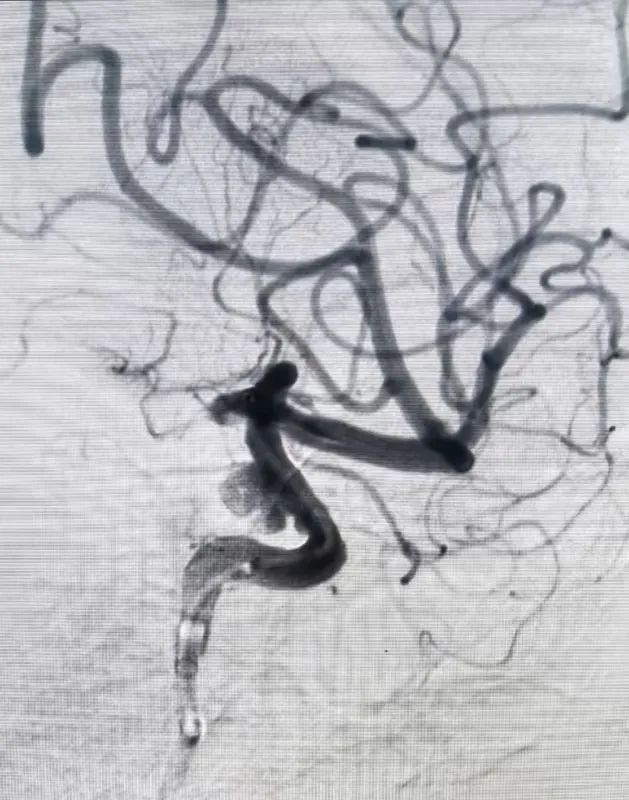

面对大动脉瘤且血管条件差的患者(腹主动脉S型迂曲,右侧颈总动脉II型牛角弓),以及颈内动脉多发动脉瘤的不同患者(C5-C7有5枚动脉瘤),吴全主任团队运用密网支架对症治疗,用一个支架巧妙解决大动脉瘤或多个动脉瘤难题,效果良好,患者短时间内快速恢复。

对于非责任动脉瘤的处理,医生们更是展现出专业与耐心。9个月前,患者动脉瘤破裂出血,当时造影发现2处动脉瘤,术中优先处理责任动脉瘤,待患者身体恢复后择期处理非责任动脉瘤。此次处理非责任动脉瘤,手术中造影,发现责任动脉瘤栓塞术后复发(3月前复查尚无),医生们当机立断,同期处理两个动脉瘤,省钱的同时,也成功为患者解除隐患。